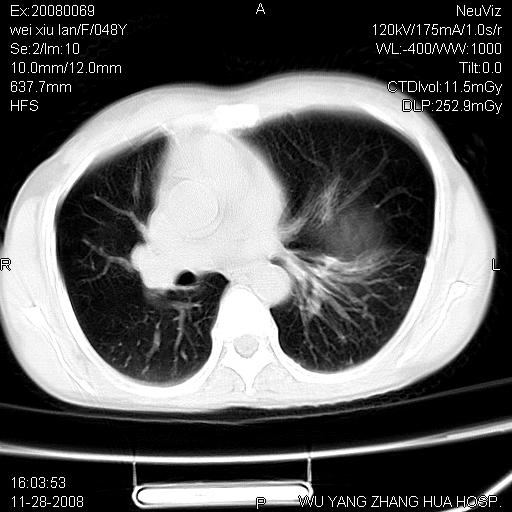

标题: CT16847:女,48岁,咳嗽,发热两日,平常偶有上腹部不适。 [打印本页]

标题: CT16847:女,48岁,咳嗽,发热两日,平常偶有上腹部不适。

能否考虑食管裂孔疝?请老师们多多指教。

胃、脾脏及部分肠管明显升高,并压迫心脏移位,

首先考虑:左侧膈疝。

左侧胸腔内见胃肠及脾脏影

支持膈疝

支持左侧膈疝,心脏受压右移.

左下肺不张、膈膨升,胸腔胃

这个是左侧膈膨升伴不完全性胃翻转,手术将松弛的左横膈膜折叠缝合即解决问题。

左膈顶及肋膈角均上移,膈面光滑,考虑左膈肌麻痹